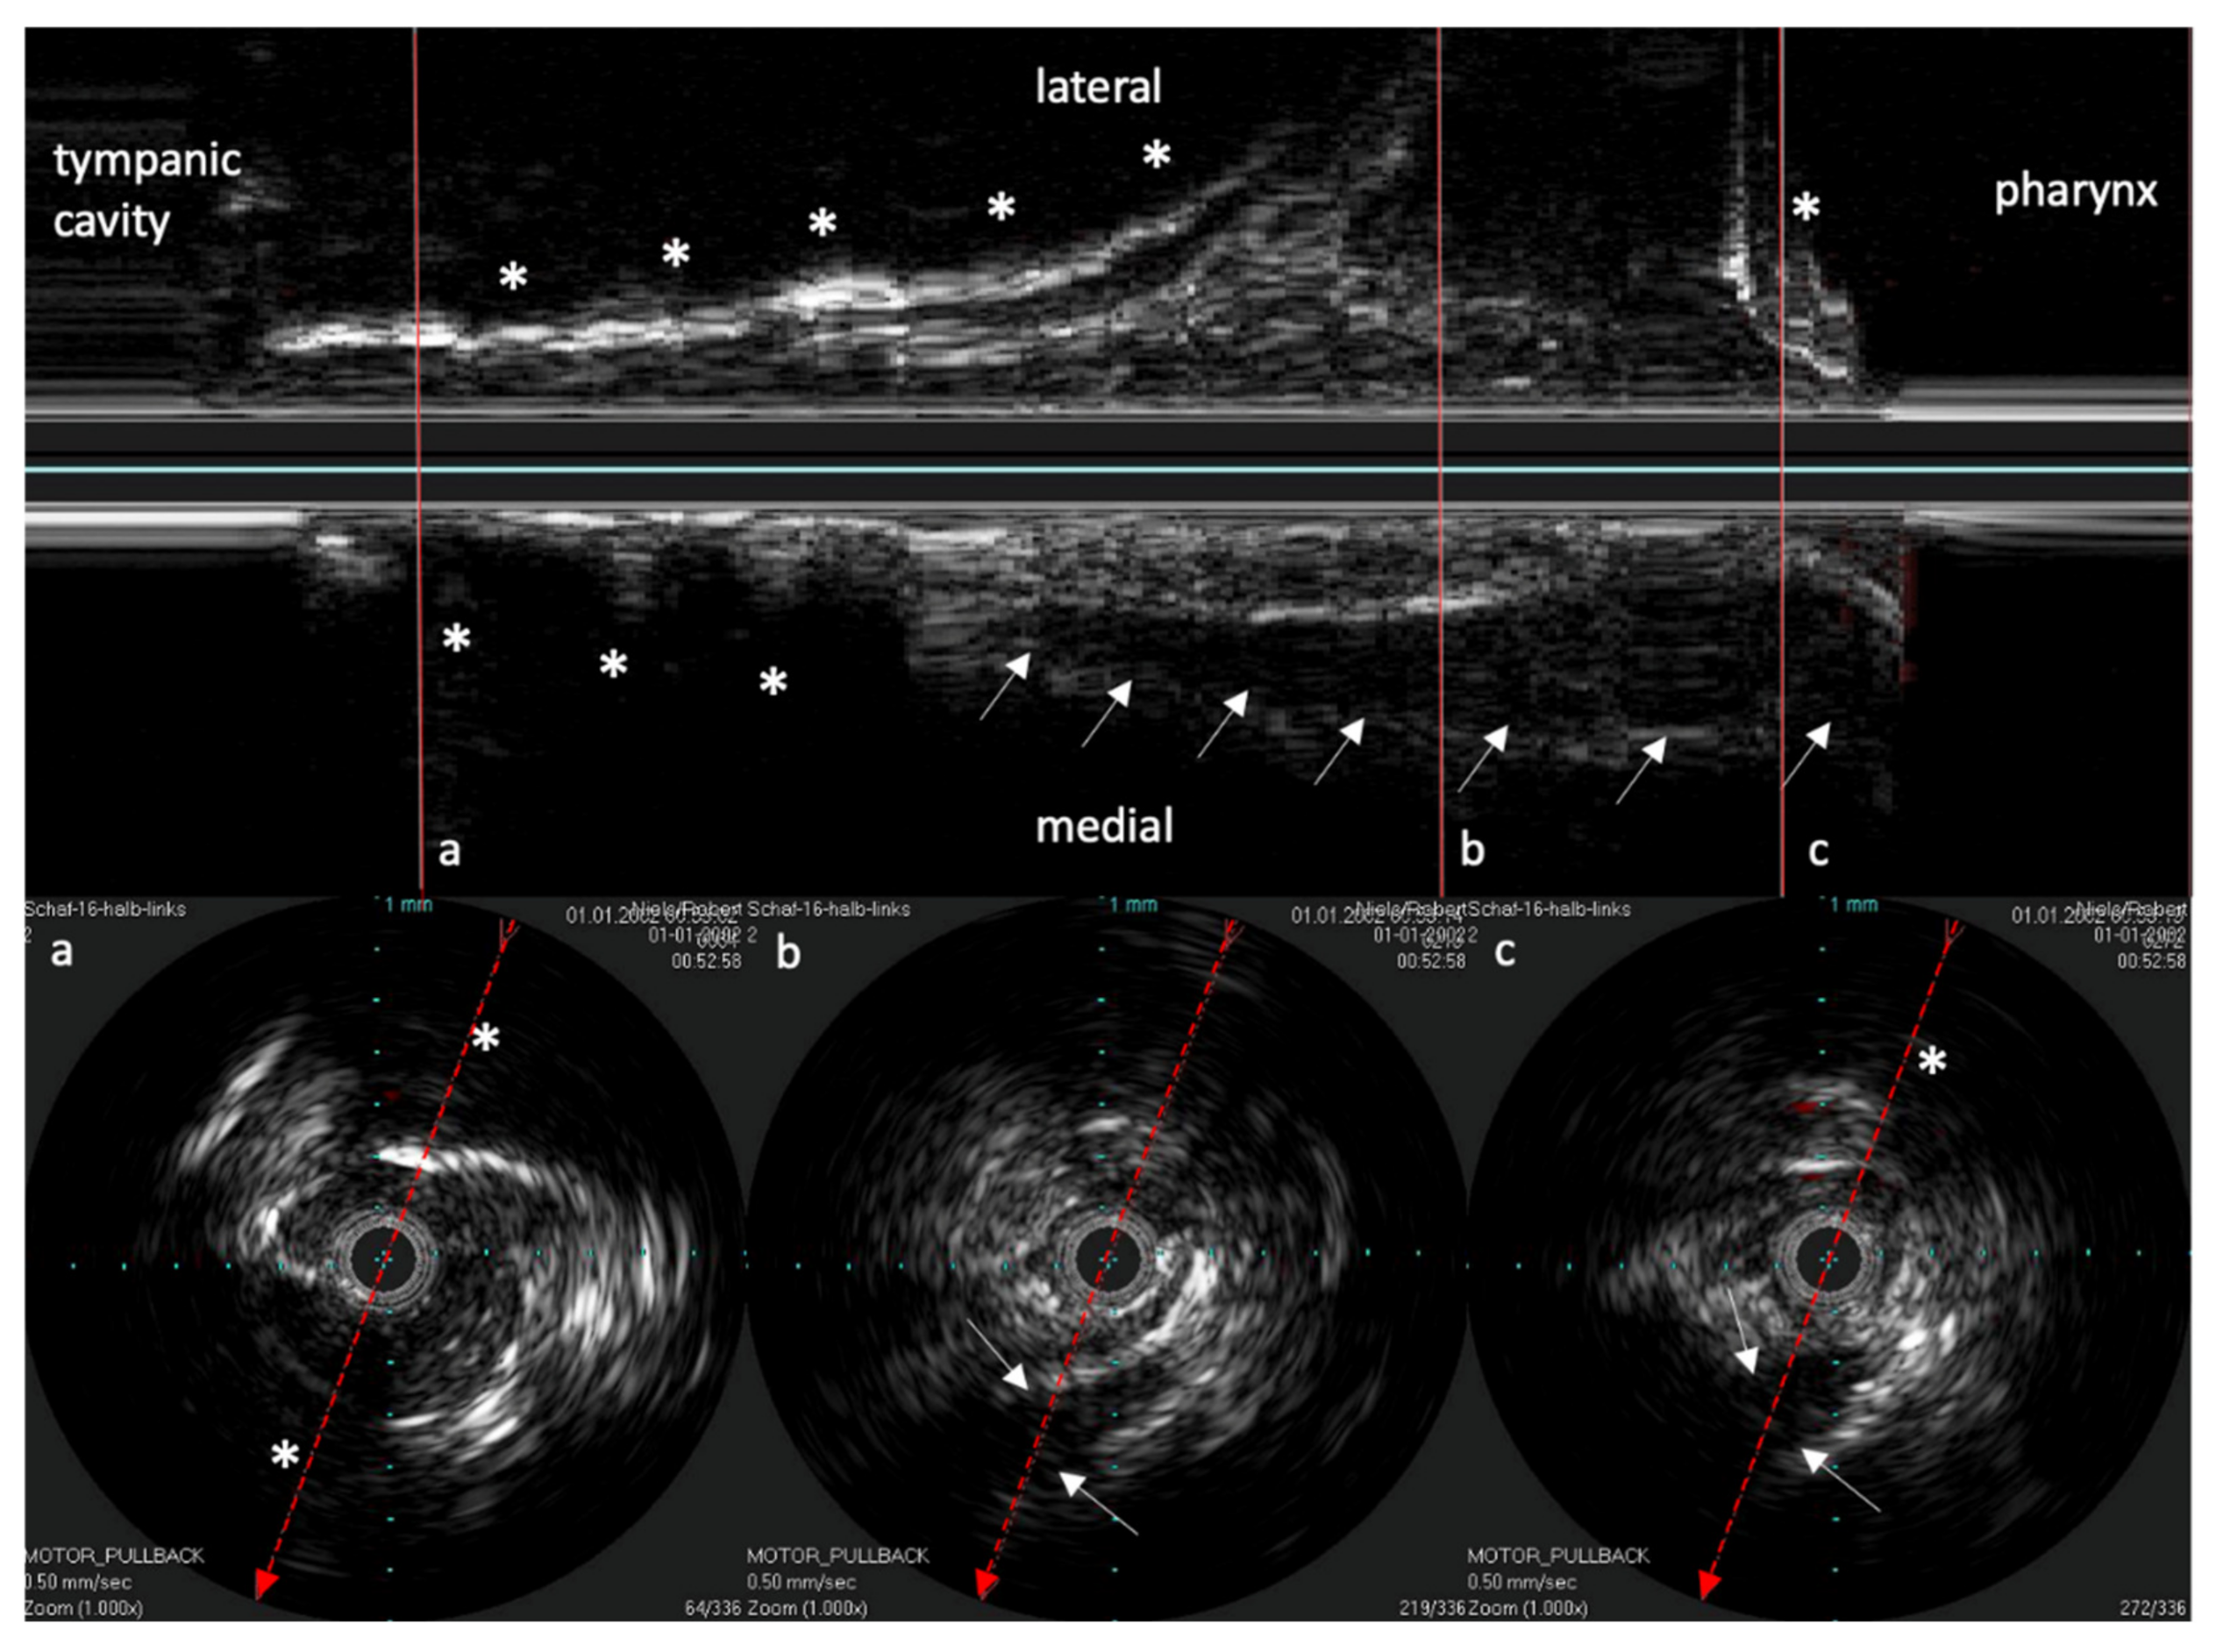

The IVUS provided a good image of the slit-formed shape of the ET (Figure 1) and the bony part with the isthmus (Figure 2) in the cross-section view. Bony structures and cartilage can be distinguished from the muscles and the Ostman fat pad. The signal transmission from the catheter to the tissue appeared to be good in all cases, even though the mucosal layer also caused some intense reflections. By flushing the ET with water (Figure 3), the lumen was more visible and became spindle shaped. Reflections at the mucosal layer were reduced.

Figure 4. Longitudinal image of the ET with the corresponding cross sections. (a) near the ET isthmus. (b) in the middle section of the ET. (c) near the pharyngeal ostium. Bone is marked with *. The bony structures represent consistent topographic landmarks. The cartilage of the ET shows low echogenicity (white arrows). Note that the dashed red line in the cross-sectional image represents the axis of the longitudinal image. The tip of the arrow points toward the lower part of the longitudinal image.